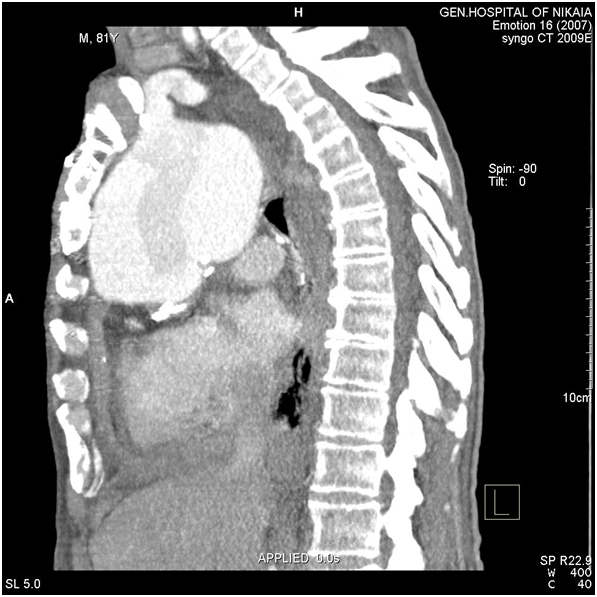

Figure 6 CT-angiography, lateral view: Aneurysm’s size and its adjacency to brachiocephalic artery and surrounding structures are depicted.

Figure 7 3-Dimentional CT-scan reconstruction of ascending, arch and descending thoracic aorta.